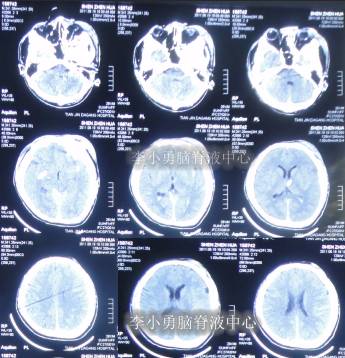

2012年9月11日,入院时:神志模糊,反应迟缓。头颅额部右侧手术瘢痕,双眼睑轻度浮肿,左眼眶凹陷,两侧瞳孔对光反射右侧存在,左侧消失,大小便失禁,体温高达39.5°C,发病以来体型消瘦,不能遵嘱活动,刺痛后四肢有反应但无发声,不能言语,饮食差,四肢肌张力增高,左上肢肌屈曲强直,余肢体肢活动受限,肌力3级(图-13),头部CT示脑干弥漫性皱缩损伤后,脑积水(图-14)。

图-13:2012年9月11日入院时

图-14:2012年9月11日头部CT